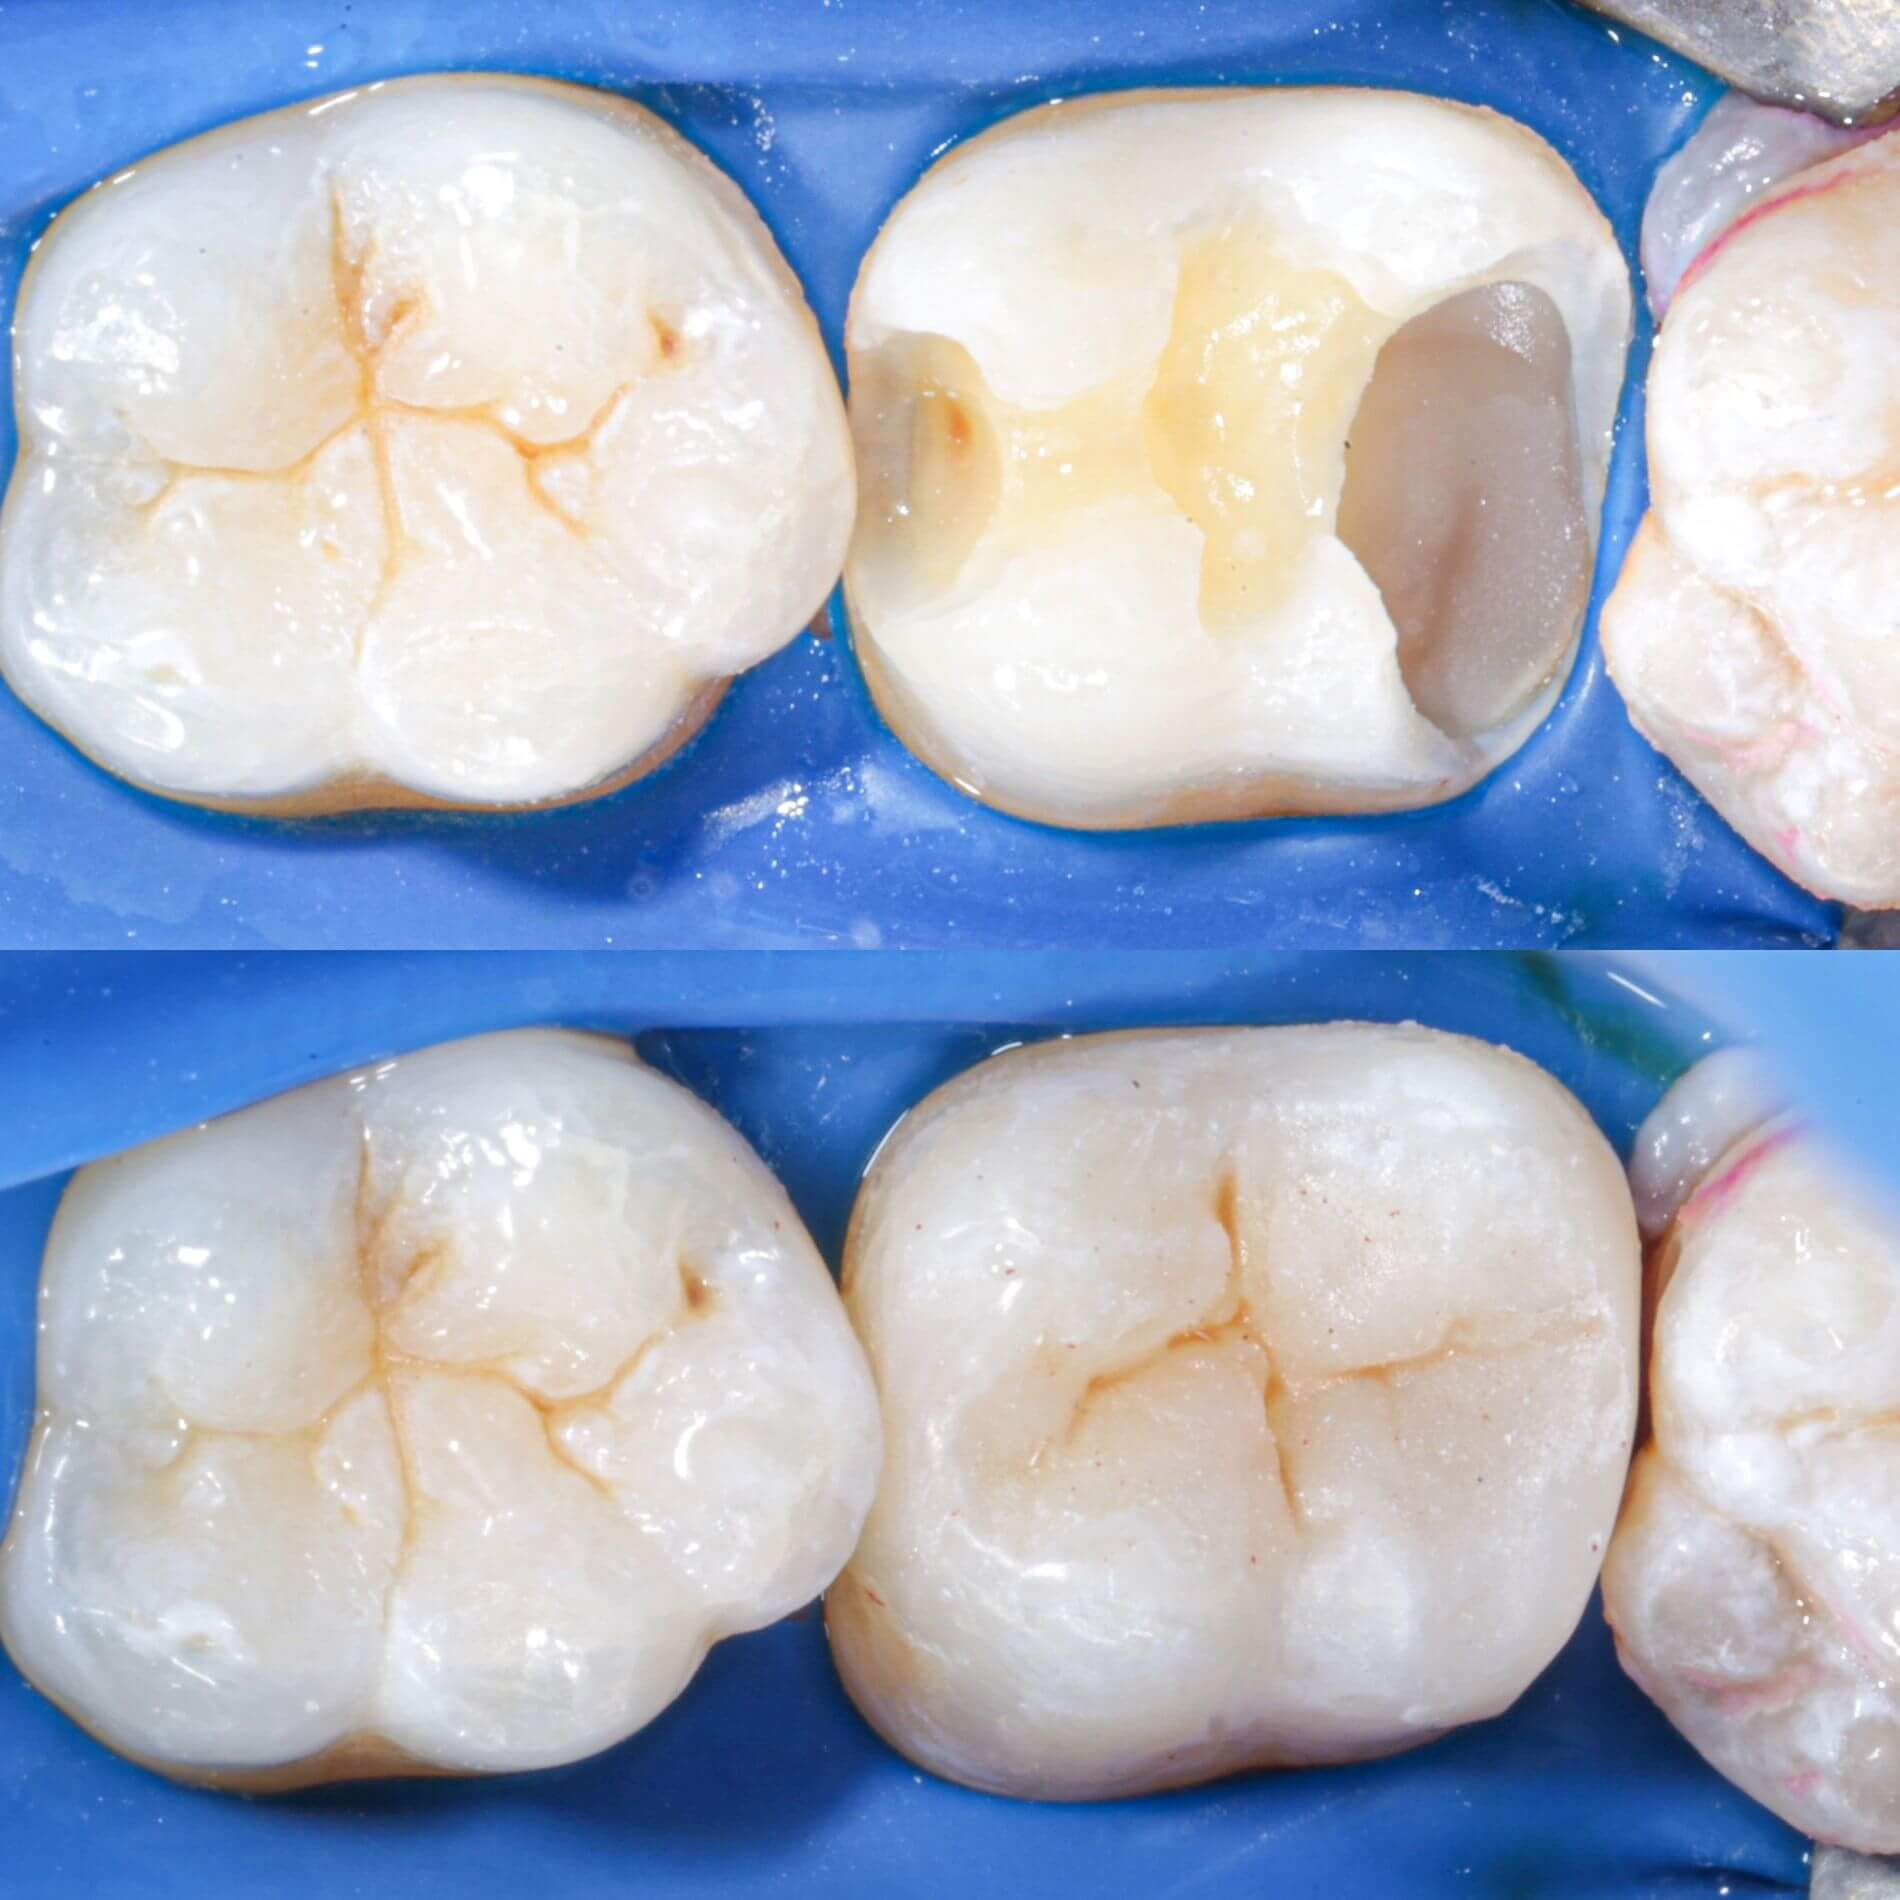

Пломбування зубів - процедура доволі земна та стандартна. Зубна порожнина заповнюється пломбувальним матеріалом та здійснюється відновлення анатомічної форми зуба. Завдяки цьому нам вдасться зберегти твій зуб і запобігти поширенню шкідливих бактерій вглиб зубу та далі по ротовій порожнині. Встановлення пломби - це оптимальний спосіб лікування карієсу і фінальний етап лікування пульпіту. Процес пломбування зуба відрізнятиметься в залежності від техніки та призначення пломби.

Колись давним-давно, в земних стоматологіях ставили цементні пломби. Думаємо, цей незабутнє відчуття «піску» після процедури багатьох переслідує досі. На щастя, ці часи минули, і тепер для твоїх зубів нас є крутий фотополімерний матеріал з космічними наночастинками. Він не тільки дуже міцний, а й гарно світиться ночами(це звісно ж жарт). Це просто найінноваційніший пломбувальний матеріал з усіх, що існуюють на ринку.

- Постійні. В Космічній стоматології Драганчука ми застосовуємо дуже крутий пломбувальний матеріал з наночастинками. За міцністю він не поступається найміцнішим метеоритам нашої галактики, тож відмінно витримує значні жувальні навантаження. Ще один особливо важливий момент - відмінні естетичні характеристики, що дозволяє ставити такі пломби не лише в жувальній зоні, а й на передній зубах.

- Кращі фотополімерні матеріали з наночастиками: пломба ідеально пасуватиме за кольором, формою, міцністю.

Лікування зубів у Космічній стоматології Драганчука передбачає використання інноваційних фотополімерних матеріалів з наночастинками. Ці матеріали дозволяють проводити лікування зубів малоінвазивно, точно, надійно і довговічно. Пломба ідеально пасує по кольору, формі та міцності.

Галерея